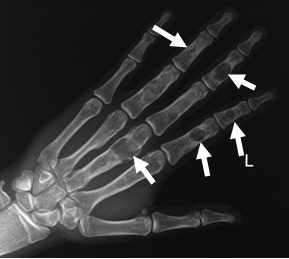

Die Diagnose erfolgt durch verschiedene Bildgebungsverfahren und bei nicht eindeutiger Situation zusätzlich durch eine geschlossene bzw. offene Probeentnahme. Das gewonnene Material wird anschließend mikroskopisch durch den Pathologen am Universitätsklinikum Ulm analysiert. Bei ausgefallenen Tumoren gibt es sog. Referenzpathologen, die deutschlandweit Zweitmeinungen abgeben, um eine optimale Diagnosestellung zu gewährleisten. Idealerweise führt die Klinik, die die Probeentnahme vorgenommen hat, auch die definitive Tumoroperation durch.

In unserer Klinik stehen folgende Verfahren zur Bildgebung zur Verfügung:

„Klassisches“ Röntgen

Röntgendurchleuchtung

Ultraschall

Computertomographie (CT) inklusive CT-gestützter Interventionen

Kernspintomographie (NMR / MRT)